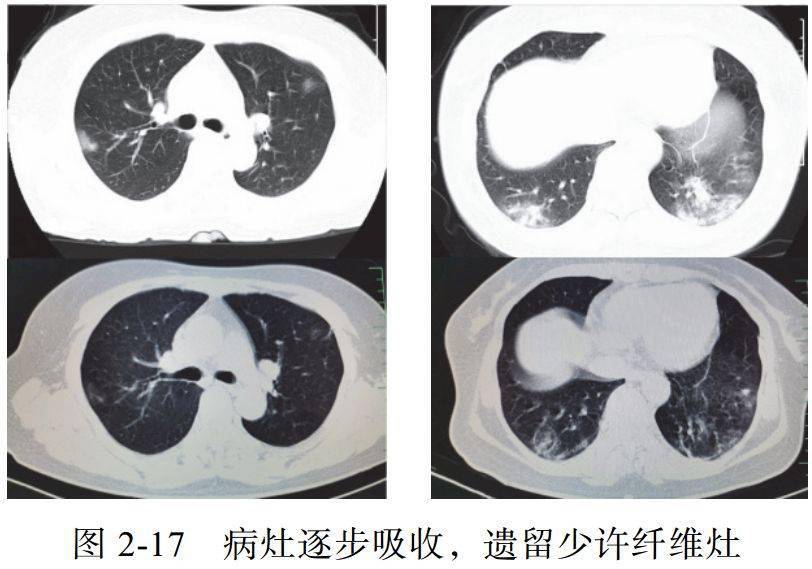

四、消散期征象

多数病例在 14 天后进入病灶消散期,表现为病灶逐步吸收,可遗留少许条索状高密度影,提示纤维化。少部分病例病程较短,影像可由早期表现直接进入消散期(图 2-17)

病例展示

4. 消散期片状 GGO 可完全吸收,肺内病灶向纤维化演变